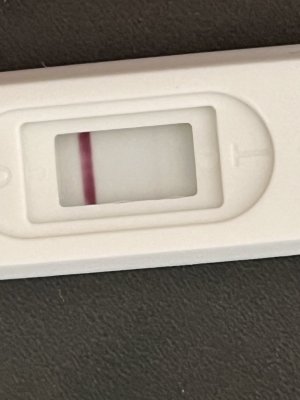

Kızlar merhaba bugün aşılamanın 11.günü yapıldığı günü saymazsam eğer , cuma günü kan vermiştim beta 0 çıkmıştı . Bugün bi test yapayım dedim testte böyle silik çizgi çıktı adetimi de tam kestiremiyorum pcos var bende 1-2 en fazla 3 gün kalmıştır. Testi ekliyorum böyle silik öğrenen varmı aranız da ?

Eklentiler

bence bebek var canım rabbim en hayırlısından nasip etsinKızlar merhaba bugün aşılamanın 11.günü yapıldığı günü saymazsam eğer , cuma günü kan vermiştim beta 0 çıkmıştı . Bugün bi test yapayım dedim testte böyle silik çizgi çıktı adetimi de tam kestiremiyorum pcos var bende 1-2 en fazla 3 gün kalmıştır. Testi ekliyorum böyle silik öğrenen varmı aranız da ?

Çok teşekkür ederim inşallahbence bebek var canım rabbim en hayırlısından nasip etsin